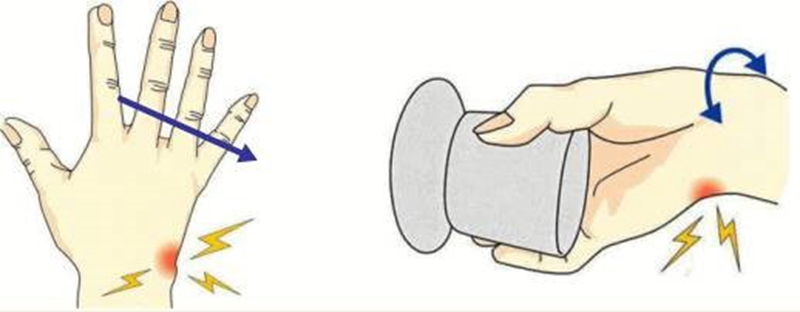

腕部三角纤维软骨复合体(TFCC)损伤是指发生于跌倒、手掌撑地、腕关节过度背伸、前臂旋前等扭转挤压的暴力致伤。轻微的TFCC损伤常被认为是腕关节扭伤,易被忽略,经久不愈会严重影响腕关节功能。

TFCC损伤机制

典型受伤机制为前臂旋前、腕关节过伸位时腕尺侧受到直接撞击或牵拉。多在以下场景受伤:网球、高尔夫球、羽毛球等运动者手腕尺侧受力和快速扭转活动;车祸中司机手握方向盘腕部受到旋转牵张暴力;突然摔倒时用手撑地;提重物不慎或手腕用力不当时扭伤等。